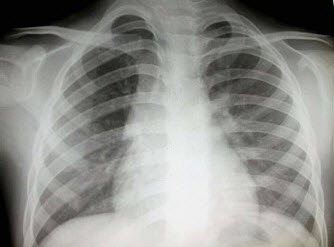

4、单项选择题

患者输液过程中突发胸闷、气急、咳痰,胸片如图,最可能的诊断为()

A.矽肺合并感染

B.中央型肺水肿

C.真菌感染

D.间质性肺水肿

E.腺病毒肺炎

点击查看答案